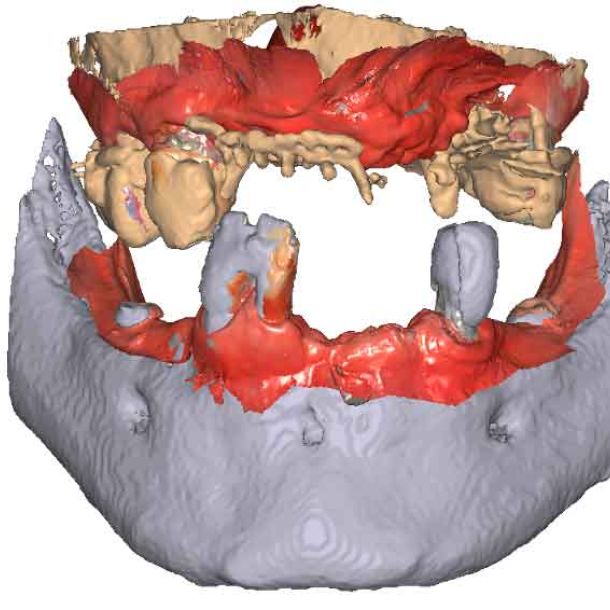

étape 2 – Acquisition du CBCT

Lorsque les scans IOS traditionnels manquent de références nécessaires, les données du CBCT peuvent servir d'alternative viable. En utilisant les fichiers du CBCT, le clinicien peut établir des références anatomiques précises pour la planification du traitement.

Pour pouvoir utiliser les données CBCT comme modèles initiaux, nous devons transformer le fichier DICOM en un fichier STL. Découvrez-en plus sur la segmentation CBCT et son utilisation dans TWIM ci-dessous.

En important les fichiers DICOM du patient au lieu des scans IOS, les cliniciens peuvent enregistrer le mouvement de la mâchoire, facilitant ainsi la planification précise du traitement.

Importez les modèles CBCT segmentés en tant que modèles initiaux dans TWIM

Sélectionnez 4 points virtuels sur la mandibule du modèle osseux importé